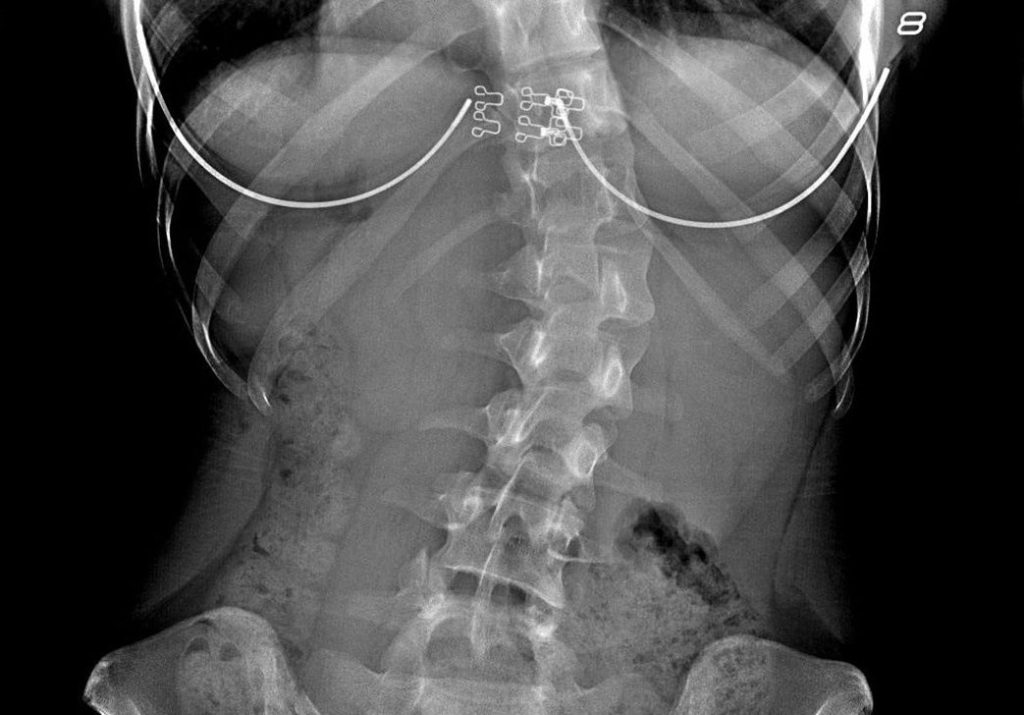

Основным методом диагностики сколиоза служит рентгенологическое обследование, которое позволяет оценить угол Кобба, отражающий выраженность искривления позвоночника. Первой стадии сколиотической болезни соответствует искривление до 9°, при последней угол Кобба превышает 75°.

Стандартная операция при сколиозе — спондилодез. Во время оперативного вмешательства с помощью специальных конструкций обездвиживаются определенные позвоночно-двигательные сегменты, что способствует сращению позвонков. В большинстве случаев такая операция эффективна, но у нее есть несколько существенных недостатков, включая ограничение потенциала роста позвоночника и свободы движений.

Недавно в России появилась альтернатива спондилодезу — вентральная динамическая коррекции позвоночника, которая может применяться как у растущих детей и подростков, так и у взрослых.

Преимущества операции — сохранение потенциала роста позвоночника, свободы движений, низкий риск кровопотери, короткий реабилитационный период. В отличие от стандартной операции, во время хирургического вмешательства мышцы спины не рассекают, поэтому пациенты очень быстро восстанавливаются. Реабилитационный период длится в среднем месяц. Через 1,5 месяца человек возвращается к неограниченной физактивности. В России первыми внедрили эту операцию в клиническую практику врачи медицинского центра им. Н.Н. Приорова.